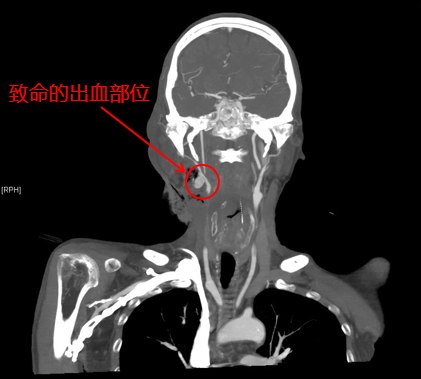

耳鼻咽喉头颈外科主治医师陈雯婧、血管外科主治医师曹战江前来急诊会诊。患者的增强CT影像显示,出血部位近动脉血管,考虑肿瘤压迫动脉导致出血。病情急而重,陈雯婧请示科主任叶京英后,认为该患者下咽癌已属晚期,不具备根治性手术机会,动脉栓塞止血应为优先考虑的方案。血管外科曹战江主治医师向科主任吴巍巍汇报了病情,决定立即为该患者进行动脉栓塞手术。